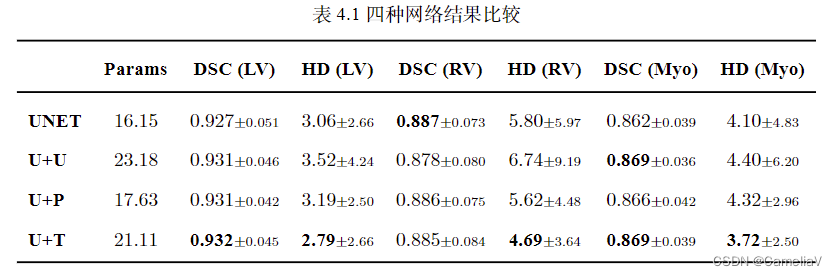

三线表效果

\begin{table}[H]

\centering

\caption{四种网络结果比较}

\label{t2-1}

\small

\begin{tabular}{lcccccccccccccccccc}

\toprule

& \textbf{Params} & \textbf{DSC (LV)} & \textbf{HD (LV)} & \textbf{DSC (RV)} & \textbf{HD (RV)} & \textbf{DSC (Myo)} & \textbf{HD (Myo)} \\

\midrule

\textbf{UNET} & $16.15$ & $0.927 \scriptstyle{\pm 0.051}$ & $3.06 \scriptstyle{\pm 2.66}$ & $\textbf{0.887} \scriptstyle{\pm 0.073}$ & $5.80 \scriptstyle{\pm 5.97}$ & $0.862 \scriptstyle{\pm 0.039}$ & $4.10 \scriptstyle{\pm 4.83}$ \\

\textbf{U+U} & $23.18$ & $0.931 \scriptstyle{\pm 0.046}$ & $3.52 \scriptstyle{\pm 4.24}$ & $0.878 \scriptstyle{\pm 0.080}$ & $6.74 \scriptstyle{\pm 9.19}$ & $\textbf{0.869} \scriptstyle{\pm 0.036}$ & $4.40 \scriptstyle{\pm 6.20}$ \\

\textbf{U+P} & $17.63$ & $0.931 \scriptstyle{\pm 0.042}$ & $3.19 \scriptstyle{\pm 2.50}$ & $0.886 \scriptstyle{\pm 0.075}$ & $5.62 \scriptstyle{\pm 4.48}$ & $0.866 \scriptstyle{\pm 0.042}$ & $4.32 \scriptstyle{\pm 2.96}$ \\

\textbf{U+T} & $21.11$ & $\textbf{0.932} \scriptstyle{\pm 0.045}$ & $\textbf{2.79} \scriptstyle{\pm 2.66}$ & $0.885 \scriptstyle{\pm 0.084}$ & $\textbf{4.69} \scriptstyle{\pm 3.64}$ & $\textbf{0.869} \scriptstyle{\pm 0.039}$ & $\textbf{3.72} \scriptstyle{\pm 2.50}$ \\

\bottomrule

\end{tabular}

\end{table}

简要说明:

\textbf 用于加粗

表格一次填入一行的数据,通过\\切换输入至下一行,通过&分割每一列输入,通过$$可以放入其他指令,如\pm代表加减号,\scriptstyle用于将加减号与数字小写,\label用于命名表格在文档里的标记,用于配合\cite引用,\caption写明表头。